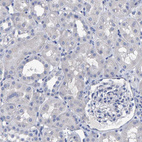

Immunohistochemistry analysis in human bone marrow and cerebral cortex tissues using HPA019572 antibody. Corresponding HEMGN RNA-seq data are presented for the same tissues.